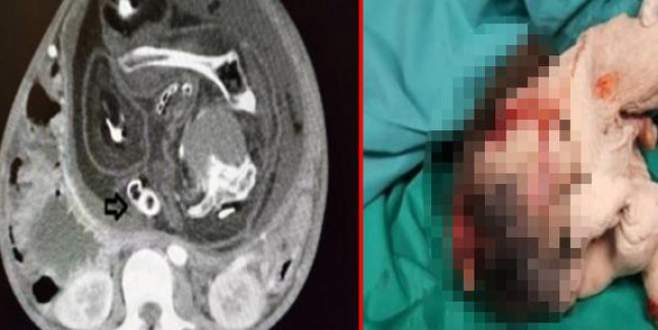

Midesi bulanıyordu! Karnından ikiz kardeşi çıktı…

Malezya'da sürekli mide bulantısı yaşamaktan şikâyet eden 15 yaşında bir çocuk hastaneye gitti. Sultan Abdul

05 Ekim 2017 Perşembe 11:50